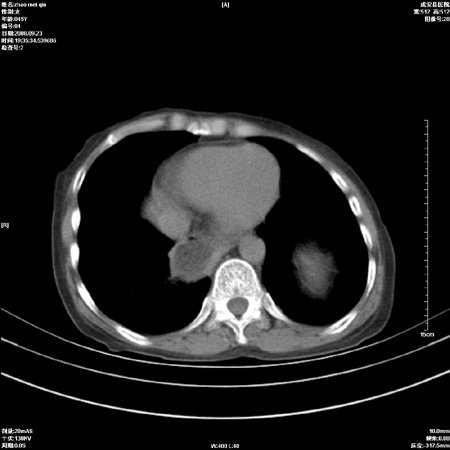

标题: CT15861:女 60 外伤后1小时 胸疼 [打印本页]

标题: CT15861:女 60 外伤后1小时 胸疼

外伤后1小时 胸疼 是外伤后引起的吗?

食道扩张明显下端逐渐变窄,倒像贲门失迟缓

非外伤性改变,典型的贲门失迟缓症

食道扩张明显下端逐渐变窄,大量食物存留,象贲门失迟缓症。